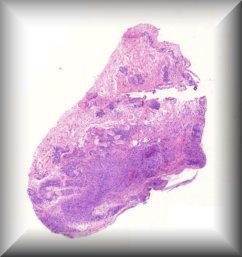

Francesc Tresserra (Guest): 26 year old male with history of Von Hipple Lindau syndrome. Enucleation of the left eye was performed. |